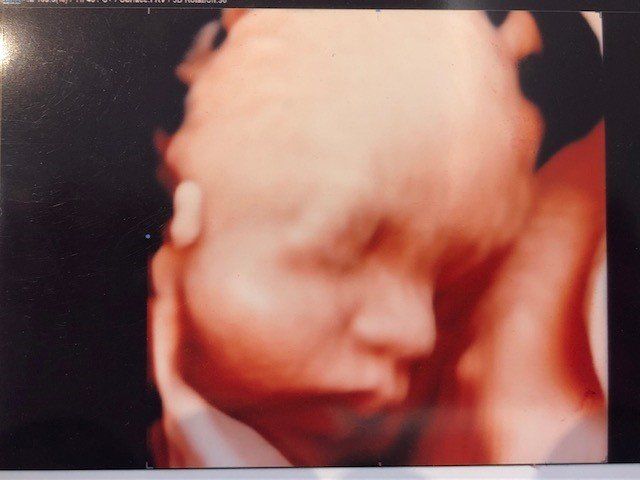

e’ specializzato in Ostetricia e Ginecologia. In campo Osterico esegue Ecografie del Primo trimestre, screening, esame premorfologico della gravidanza a rischio, ecografia morfologica di primo e secondo livello con studio cardiaco fetale, ecoflussimetria, valutazione ecografica in 3d e 4d con registrazione su supporto digitale DVD o Pen Drive per le pazienti. In campo ginecologico ecografia di primo, secondo livello e studio delle Masse Ovariche secondo le linee guida internazionali IOTA.

Lo specialista in Ostetricia per le pazienti in dolce attesa propone un piano di controllo estremamente dettagliato, ad esempio oltre alla classica ecografia che solitamente viene eseguita nei primi mesi della gravidanza, si esegue anche l'esame premorfologico per le gravidanze a rischio, in modo da valutare fin dai primi mesi la probabilità di malformazioni ed ecografia 3d e 4D con registrazione su supporto digitale delle immagini e del suono del battito cardiaco. Si effettua lo studio cardiaco fetale, tutto ciò consente di monitorare e tutelare la salute della madre e del bimbo.